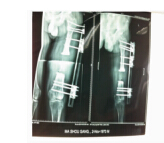

图 7 术后X线片

图 8 术后7个月